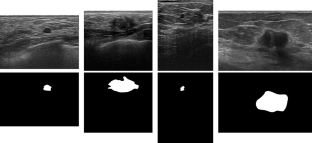

Detecting breast lesions using ultrasound imaging is an important application of computer-aided diagnosis systems. Several automatic methods have been proposed for breast lesion detection and segmentation; however, due to the ultrasound artefacts, and to the complexity of lesion shapes and locations, lesion or tumor segmentation from ultrasound breast images is still an open problem. In this paper, we propose using a lesion detection stage prior to the segmentation stage in order to improve the accuracy of the segmentation.

We used a breast ultrasound imaging dataset which contained 163 images of the breast with either benign lesions or malignant tumors. First, we used a U-Net to detect the lesions and then used another U-Net to segment the detected region. We could show when the lesion is precisely detected, the segmentation performance substantially improves; however, if the detection stage is not precise enough, the segmentation stage also fails. Therefore, we developed a test-time augmentation technique to assess the detection stage performance.

By using the proposed two-stage approach, we could improve the average Dice score by 1.8% overall. The improvement was substantially more for images wherein the original Dice score was less than 70%, where average Dice score was improved by 14.5%.